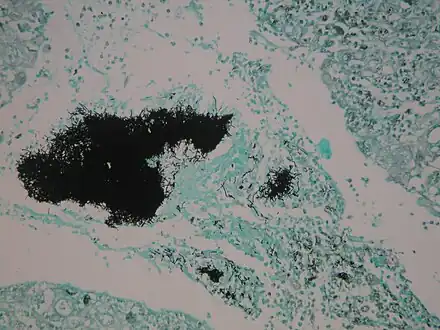

Micrograph of actinomycosis, H&E stain Micrograph of actinomycosis, GMS stain

Micrograph of actinomycosis, GMS stain Micrograph of actinomycosis, Gram stain